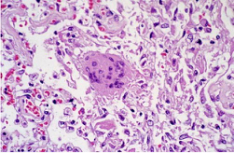

病理标本的一种,制作时将部分有病变的组织或脏器经过各种化学品和埋藏法的处理,使之固定硬化,在切片机上切成薄片,粘附在玻片上,染以各种颜色,供在显微镜下检查,以观察病理变化,作出病理诊断,为临床诊断和治疗提供帮助。

常用的染色方法是苏木素-伊红(Hematoxylin-Eosin)染色法,简称H.E染色法。这种方法对任何固定液固定的组织和应用各种包埋法的切片均可使用。苏木素是一种碱性染料,可使组织中的嗜碱性物质染成蓝色,如细胞核中的染色质等;伊红是一种酸性染料,可使组织中的嗜酸性物质染成红色,如多数细胞的胞质、核仁等在H.E染色的切片中均呈红色。